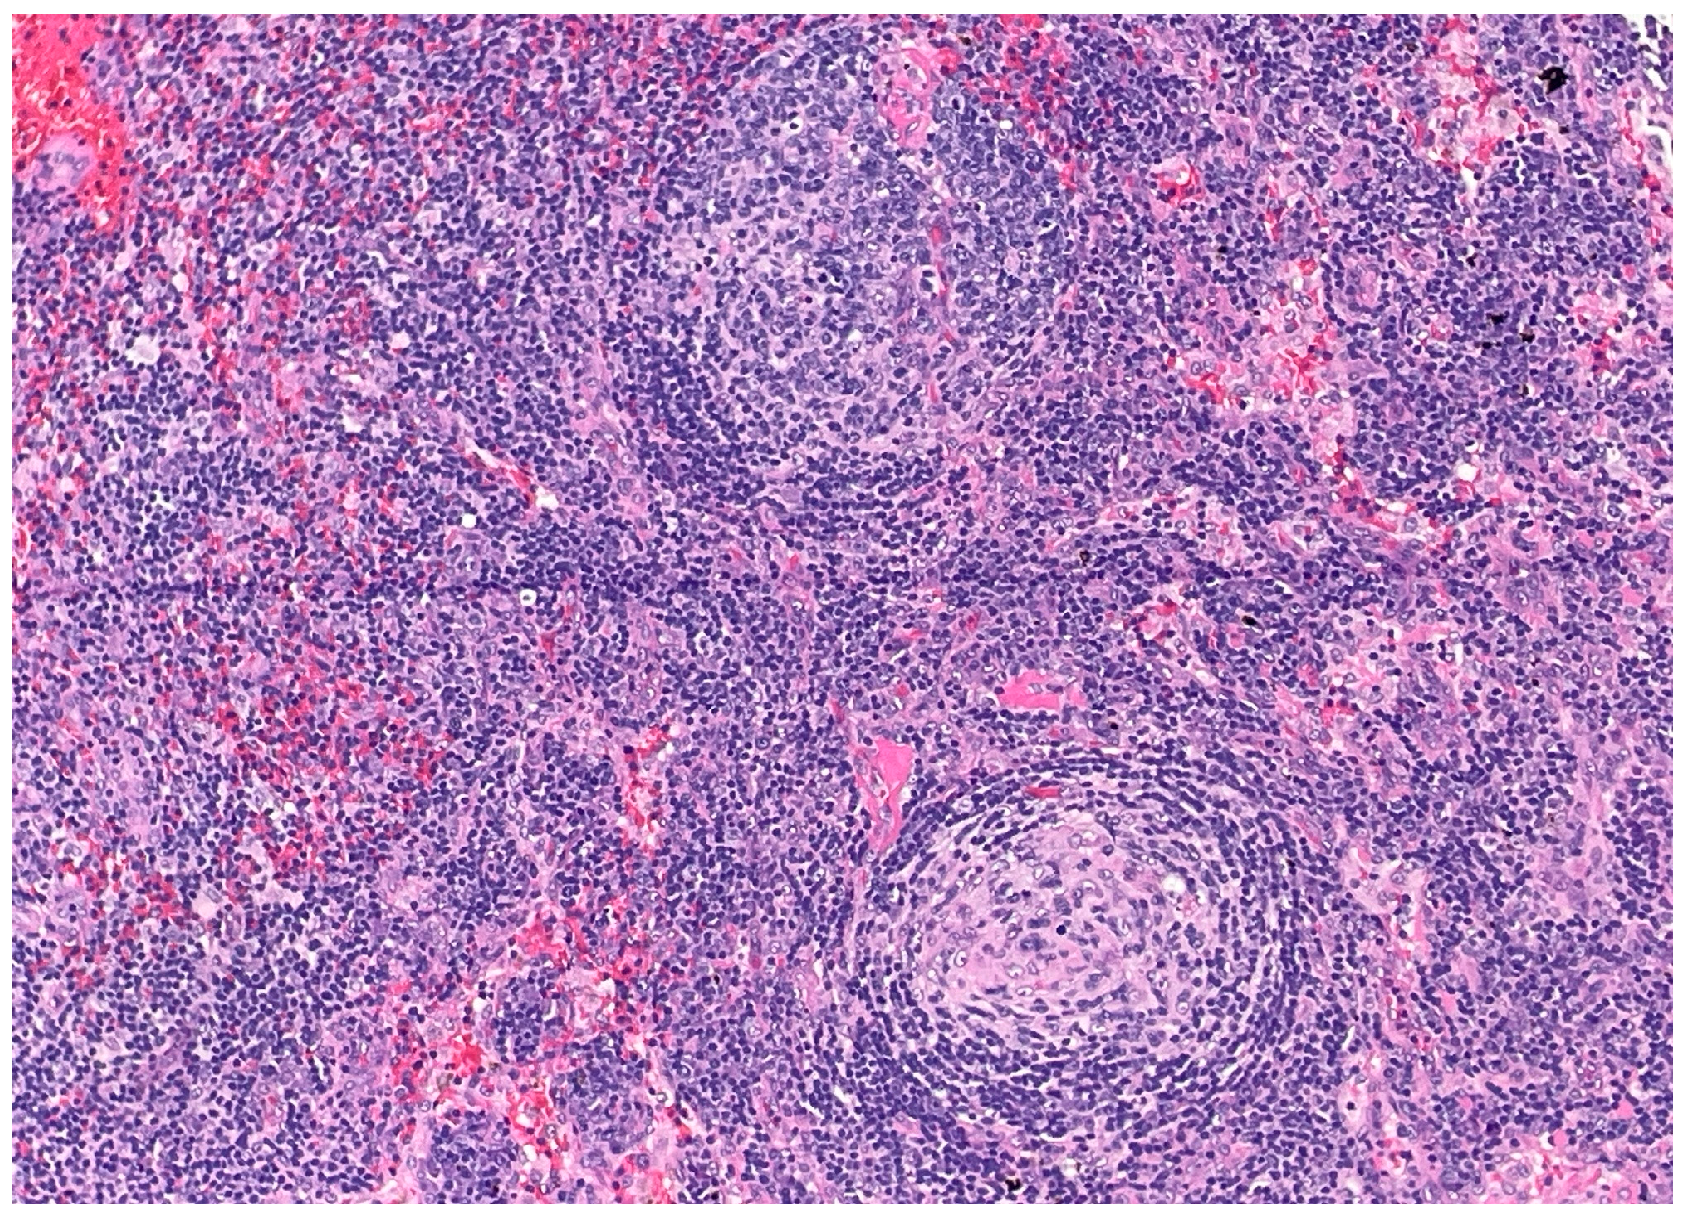

Over the following weeks, the patient developed ascites and worsening constitutional symptoms. An excisional biopsy of a lymph node was subsequently performed and demonstrated HHV-8-positive MCD, confirmed by immunohistochemical staining for LANA-1, showing scattered nuclear positivity in lymphoid cells (Figure 1). The histology also revealed characteristic “onion skinning” of mantle zone lymphocytes (Figure 2) and regressed germinal centers with increased interfollicular vascularity and hyalinization (Figure 3), findings consistent with HHV-8-associated MCD. Rituximab monotherapy was initiated, resulting in clinical improvement, resolution of the constitutional symptoms, and stabilization of ascites.

Figure 2. Higher-power view of secondary follicle showing characteristic “onion skinning” of mantle zone lymphocytes. (H&E, 20×). This histopathologic feature can be seen in all types of Castleman disease. The concentric layering of small lymphocytes around atrophic germinal centers resembles an “onion skin” pattern.

The distinction between a core needle and excisional biopsy is critical because delays in performing excisional biopsies frequently prolong the diagnostic timeline, consequently delaying the initiation of essential treatment. In accordance with published consensus criteria, the excisional biopsy for our patient not only confirmed the diagnosis, but also revealed classic MCD histopathologic features, including the characteristic “onion skinning” mantle zones and the presence of LANA-1-positive plasmablasts [1].

Figure 3. Low-power view of secondary follicles showing regressed germinal center and prominent interfollicular vascularity. (H&E, 10×). The follicle on the bottom shows an atrophic and partially hyalinized germinal center. The follicle on the top shows a vessel penetrating the germinal center (“lollipop” feature). These features can be seen in all types of Castleman disease.